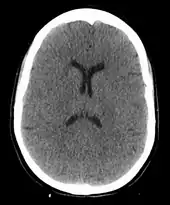

The cause of death in hanging depends on the conditions related to the event. When the body is released from a relatively high position, the major cause of death is severe trauma to the upper cervical spine. The injuries produced are highly variable. One study showed that only a small minority of a series of judicial hangings produced fractures to the cervical spine (6 out of 34 cases studied), with half of these fractures (3 out of 34) being the classic "hangman's fracture" (bilateral fractures of the pars interarticularis of the C2 vertebra).[26]

In the absence of fracture and dislocation, occlusion of blood vessels becomes the major cause of death, rather than asphyxiation. Obstruction of venous drainage of the brain via occlusion of the internal jugular veins leads to cerebral oedema and then cerebral ischemia. The face will typically become engorged and cyanotic (turned blue through lack of oxygen). Compromise of the cerebral blood flow may occur by obstruction of the carotid arteries, even though their obstruction requires far more force than the obstruction of jugular veins, since they are seated deeper and they contain blood in much higher pressure compared to the jugular veins.[28]